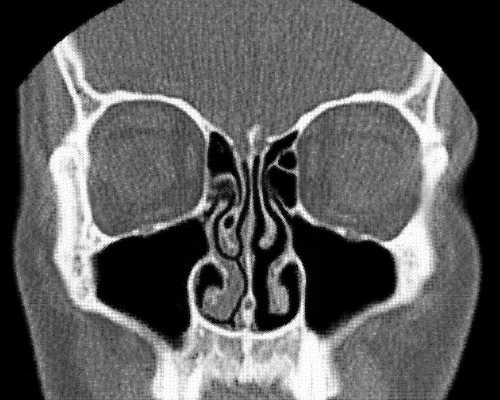

在正常状态下,我们的一个鼻孔处于主要的工作状态来进行呼吸,而另一个鼻孔的呼吸量很少,处于暂时的休息状态。过一段时间另外一只鼻孔开始工作,先前工作的鼻孔则进入休息状态。这种交替工作和休息的过程就叫做鼻循环。

也就是说,我们平时吸入和呼出的大部分气体只通过一个鼻孔进出,只有少部分气体会通过另一个鼻孔,因此两个鼻孔总是一侧通一侧相对不通。事实上,无论是正常还是感冒的状态下,鼻循环都是一直存在的。

鼻循环的时间周期一般为2个小时以上,且随着年龄的增长,循环周期也会逐渐变长,最长的甚至会达到8个小时进行一次循环。我们体内的植物性神经系统负责交换两只鼻孔的角色,保证这一交替过程的顺利完成。